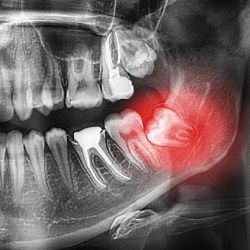

Extracción de muelas del juicio (terceros molares).

Extracción de dientes retenidos o supernumerarios.

Previene complicaciones mayores en hueso, encías o dientes vecinos